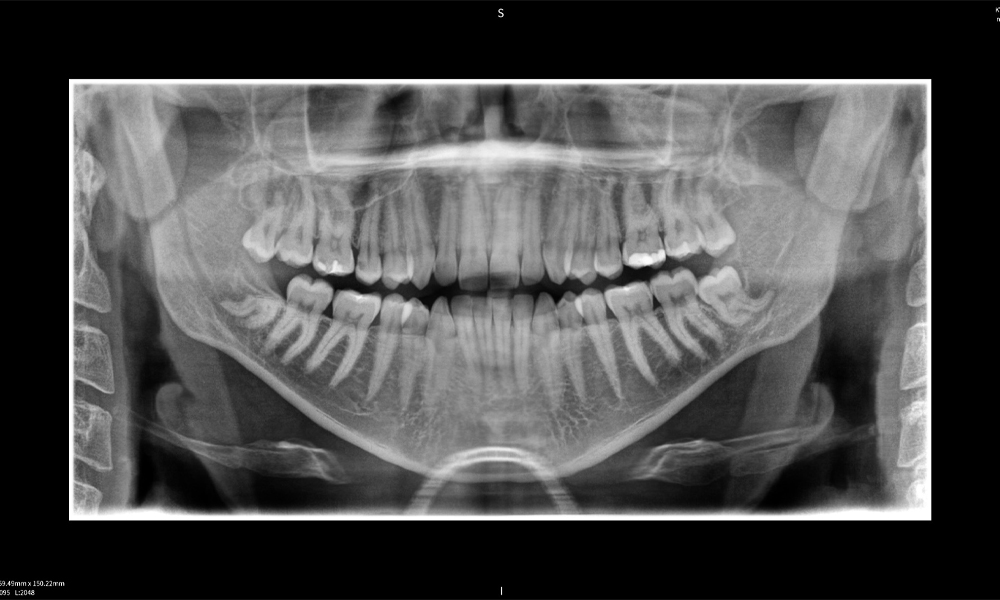

Nachstehend finden Sie einen Fall von Dr. med. dent. Oliver A. Centrella, in dem die CBCT-Aufnahmen mit Seethrough Max entscheidende Informationen zur komplexen Anatomie sowie zur kritischen Beziehung zwischen den Weisheitszähnen und dem Nervus alveolaris inferior lieferten. Bei diesem Fall besteht eine Indikation zur chirurgischen Entfernung der Weisheitszähne.

Abbildung e: Panoramaröntgenaufnahme dient der initialen Beurteilung und zeigt die allgemeine Zahnstellung sowie mögliche pathologische Veränderungen auf. Insbesondere ist auf der rechten Seite (Zahn 48) die Situation nach einer Kronenamputation durch einen externen Behandler ersichtlich. Die beiden stark gekrümmten Wurzeln verbleiben in enger topographischer Beziehung zum Nervus alveolaris inferior im Knochen. Dies deutet auf eine bewusste Entscheidung zur Vermeidung eines erhöhten Risikos einer Nervenläsion während einer vollständigen Extraktion hin und stellt einen klinisch relevanten Befund dar. Zusammenfassend liefern die CBCT-Aufnahmen mit Seethrough Max entscheidende Informationen über die komplexe Anatomie und die kritische Beziehung zwischen den Weisheitszähnen und dem Nervus alveolaris inferior. Diese detaillierte präoperative Diagnostik ist unerlässlich für die sichere und erfolgreiche Durchführung chirurgischer Eingriffe im Unterkieferbereich.